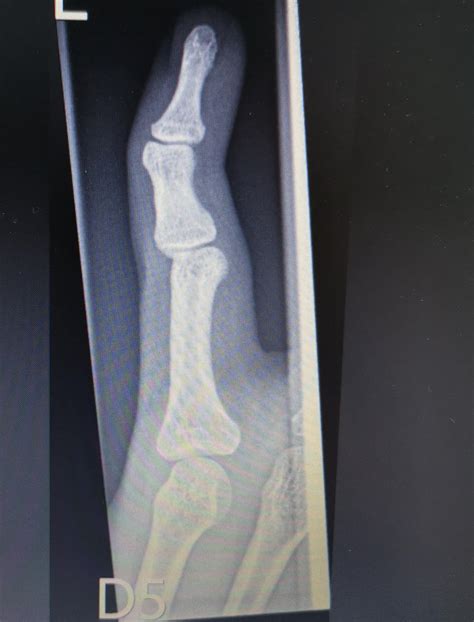

Diagnosing a dislocated pinky finger typically involves a physical examination and imaging tests. The doctor will:

• Examine the finger to assess the extent of the injury.

• Order X-rays to confirm the dislocation and rule out any fractures.

In some cases, additional imaging tests like an MRI or CT scan may be required to get a more detailed view of the injury.

• dislocated pinky finger xray